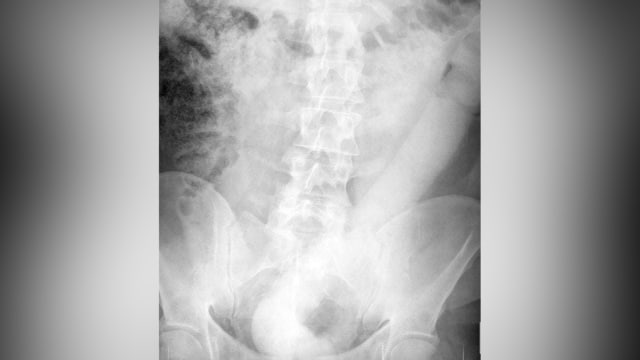

Setelah dilakukan pemeriksaan X-ray di rumah sakit, pria itu kemudian dirujuk ke bagian endoskopi.